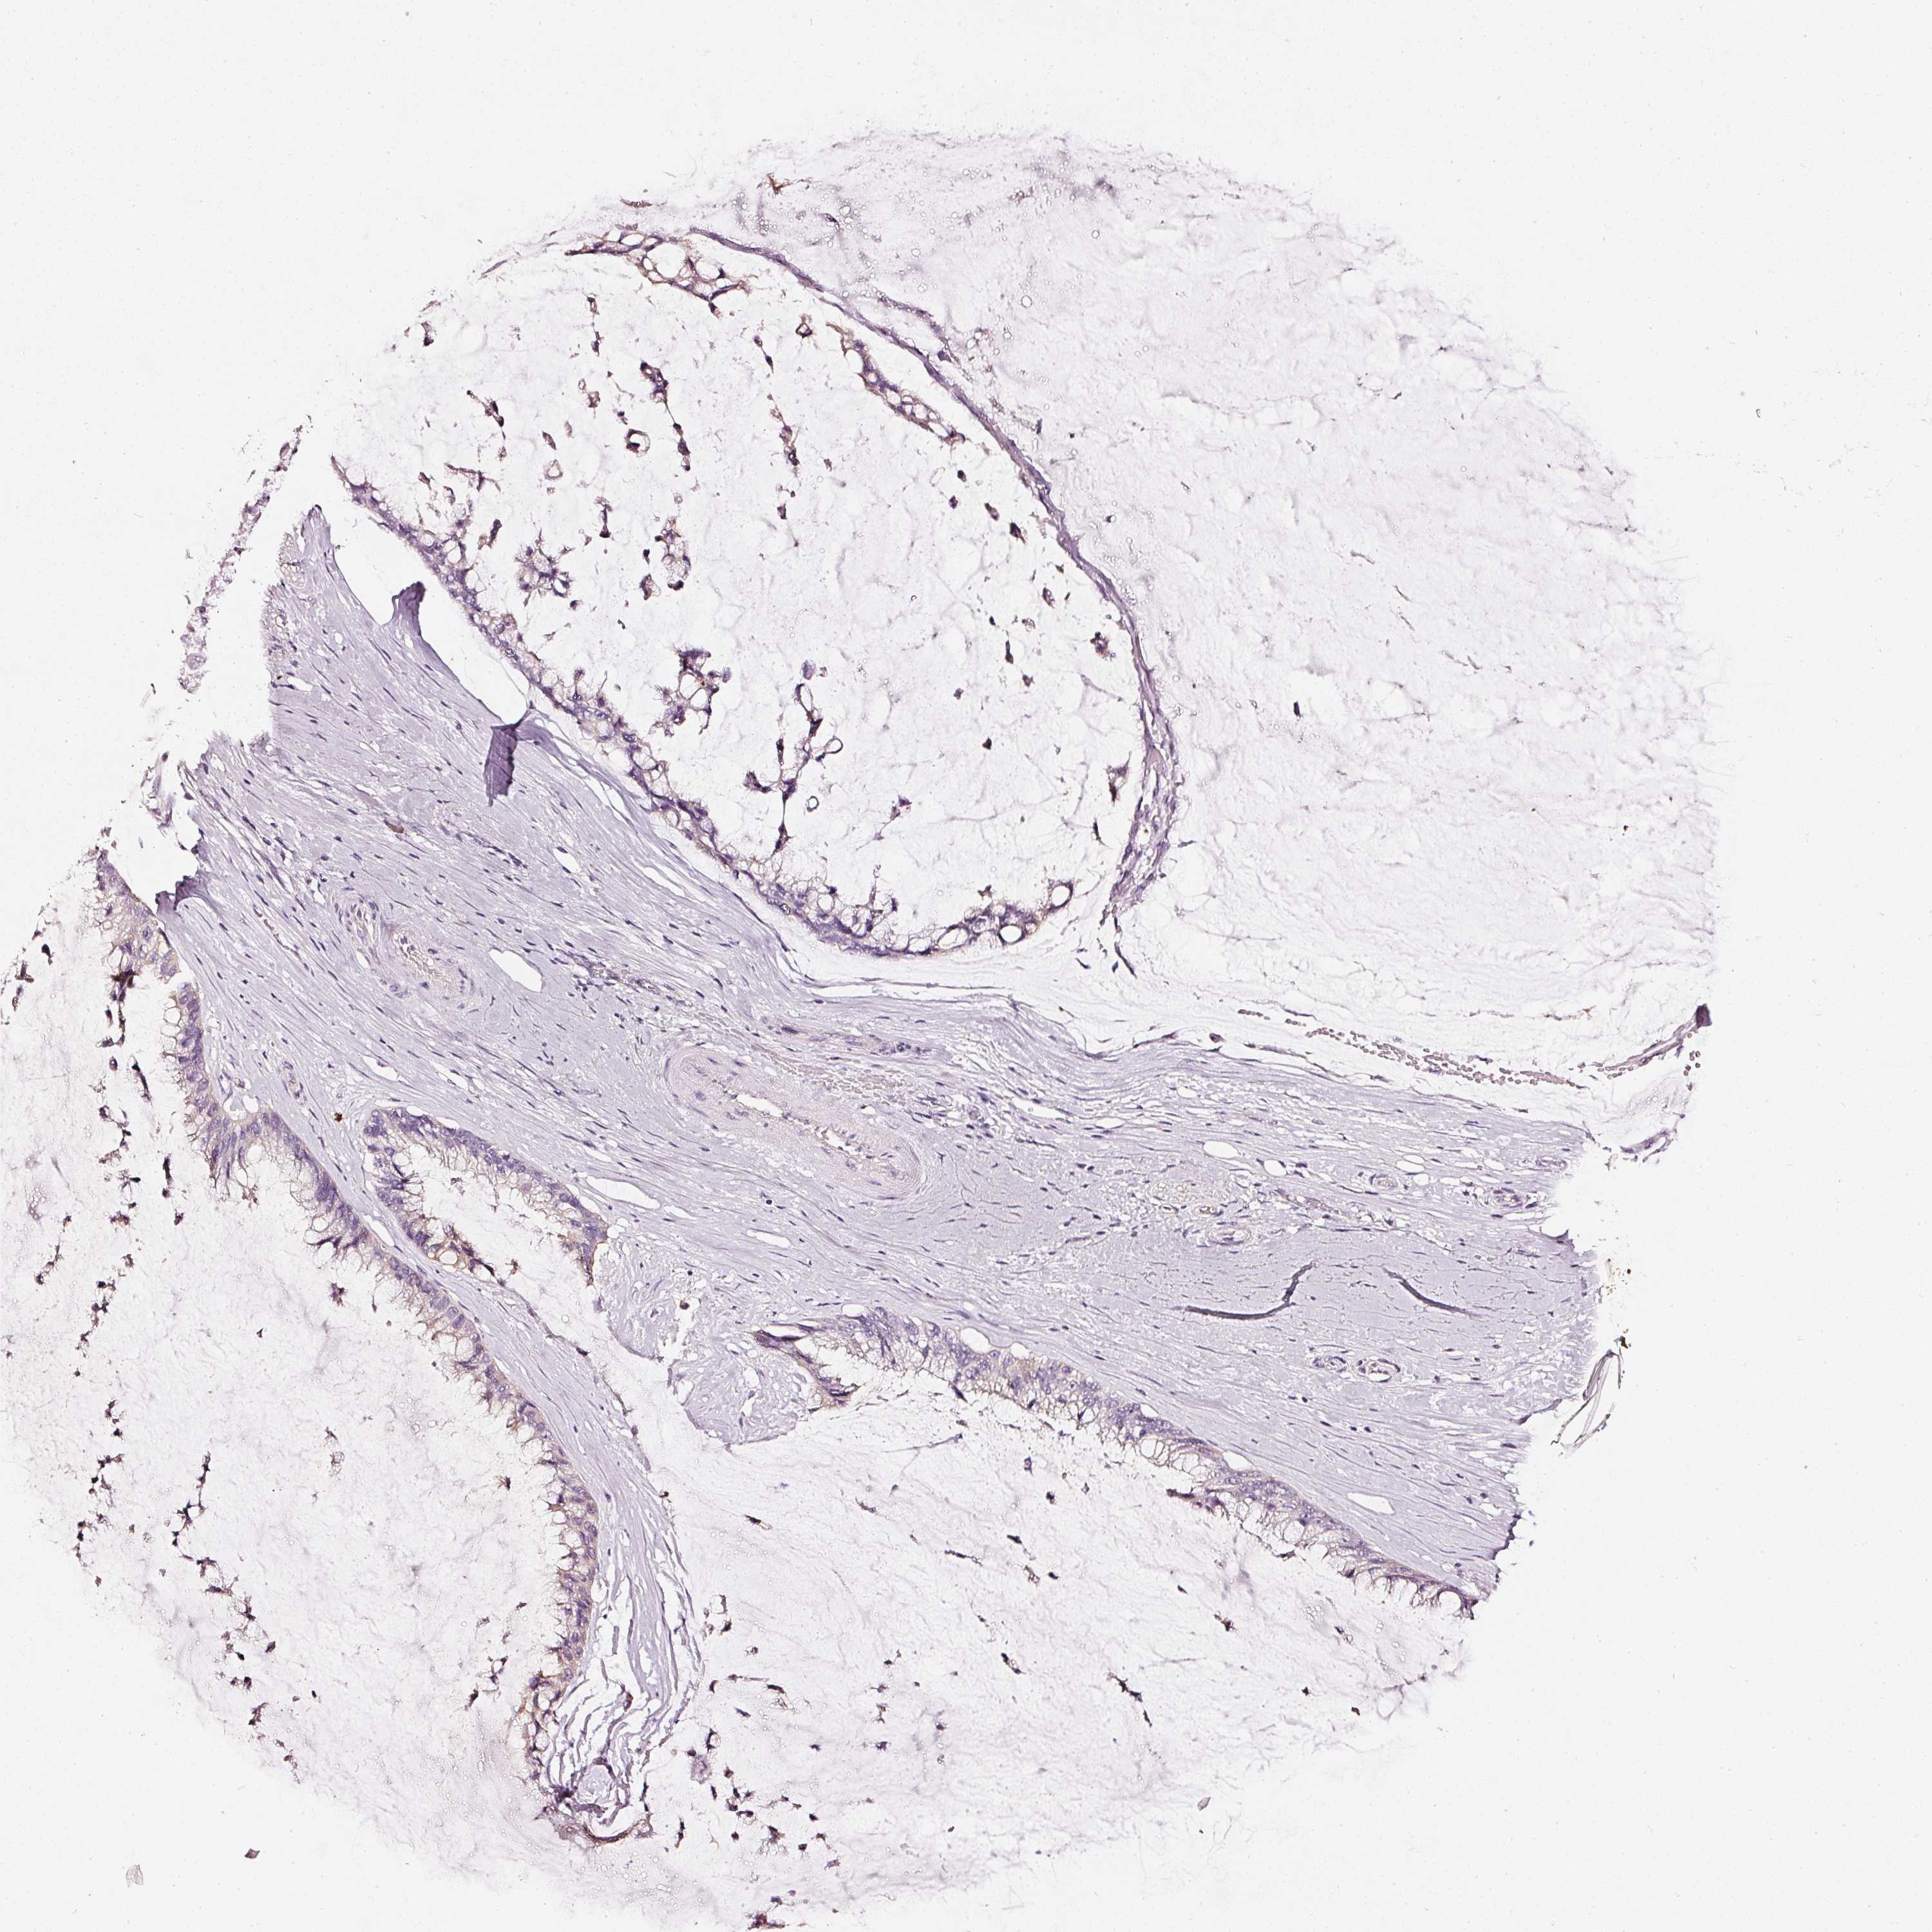

OVARIAN CANCER - Protein expressioni

A mouse-over function shows sample information and annotation data. Click on an image to view it in a full screen mode. Samples can be filtered based on level of antibody staining by selecting one or several of the following categories: high, medium, low and not detected. The assay and annotation is described here.

Note that samples used for immunohistochemistry by the Human Protein Atlas do not correspond to samples in the TCGA dataset.

Antibody stainingi

Antibody staining in the annotated cell types in the current human tissue is reported as not detected, low, medium, or high, based on conventional immunohistochemistry profiling in selected tissues. This score is based on the combination of the staining intensity and fraction of stained cells.

Each image is clickable and will lead to virtual microscopy that enables deeper exploration of all samples and also displays staining intensity scores, fraction scores and subcellular localization as well as patient and tissue information for each sample.

Carcinoma, endometroid